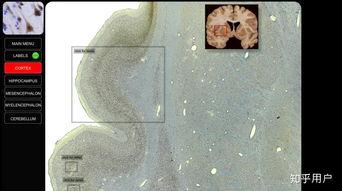

局部解剖视频以其高清的画面、逼真的解剖结构,让人仿佛置身于真实的解剖现场。这种视觉震撼,让我们对人体的奥秘有了更直观的认识。

局部解剖视频涵盖了人体各个部位的解剖知识,从骨骼、肌肉到血管、神经,无所不包。这些视频不仅有助于医学爱好者了解人体结构,还能为医学生提供实用的教学资源。